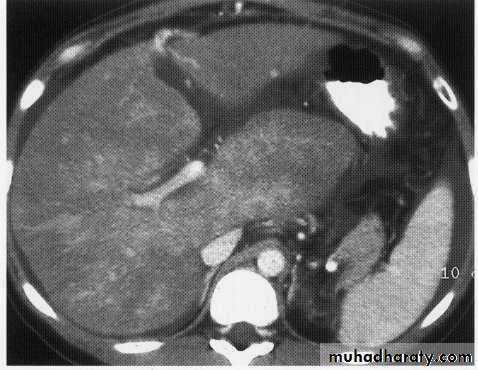

hepatic mets venous phase

Enhanced + Unenhanced CT